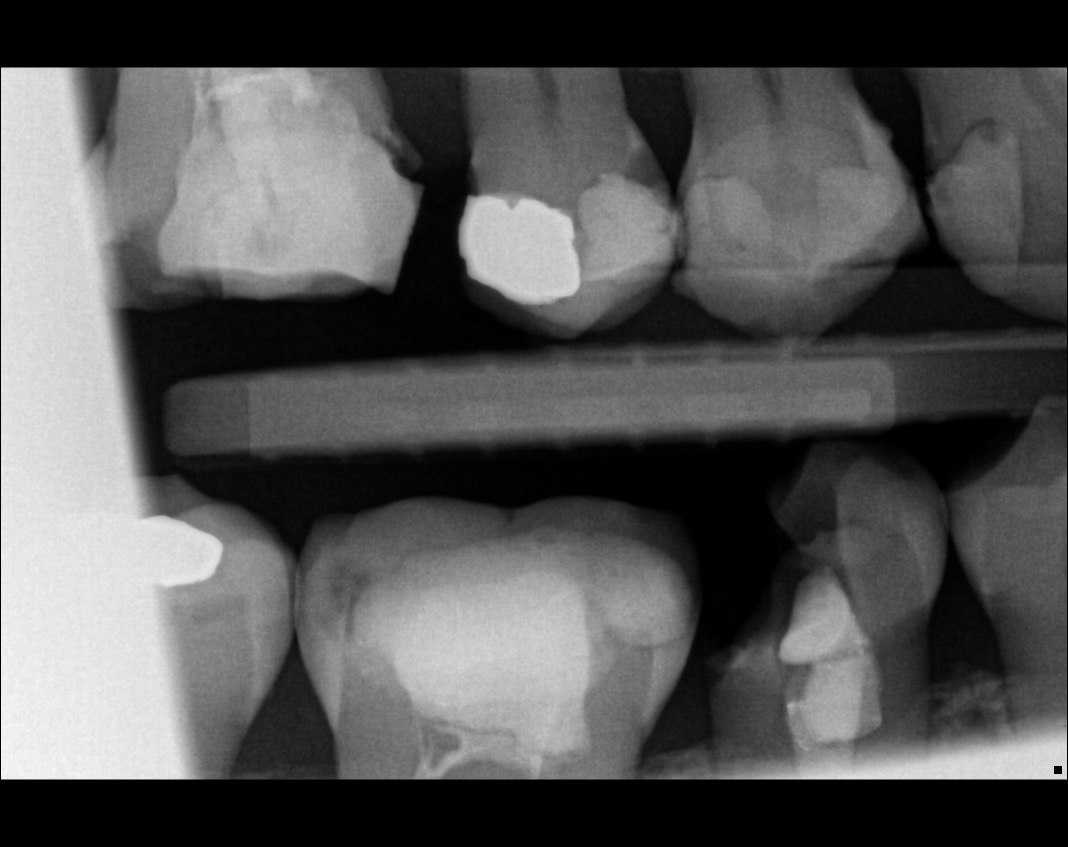

Question 1: What is the condition of the mesial surface of the tooth # 2.6?

Question 2. What is the condition of the mesial of the tooth # 2.7?

Question 3. What is the condition of the distal surface of the tooth # 2.7 and mesial surface of the tooth # 2.8 respectively?

Question 4: what is the condition of the distal of the tooth # 4.1 and mesial of the tooth #3.1 respectively?